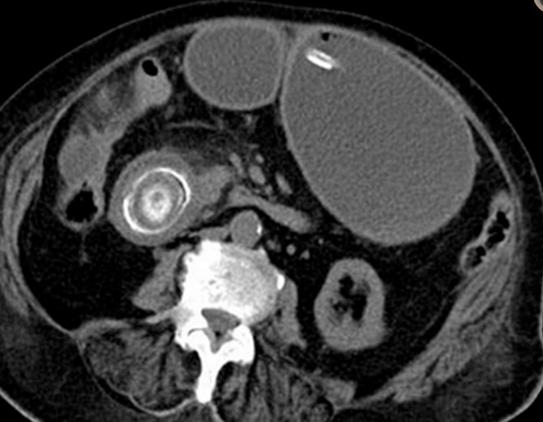

老年女性,腹痛、呕吐就诊。CT 平扫示胃腔扩张,十二指肠降部腔内见高密度结石。

老年女性,右上腹疼痛、呕吐。CT 增强示十二指肠球部结石,十二指肠球部及胆囊相通,存在瘘。